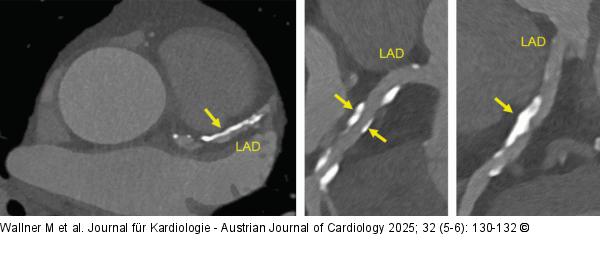

Abbildung 2: Coronary-CT Coronary-CT scan showing heavy calcified plaques in the proximal LAD |

Coronary-CT scan showing heavy calcified plaques in the proximal LAD |